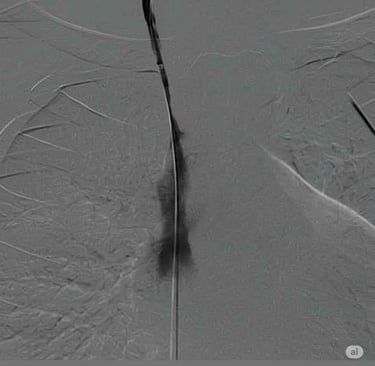

Paso de guía Amplatz Super Stiff por zona de estenosis dentro de la vaina de fibrina